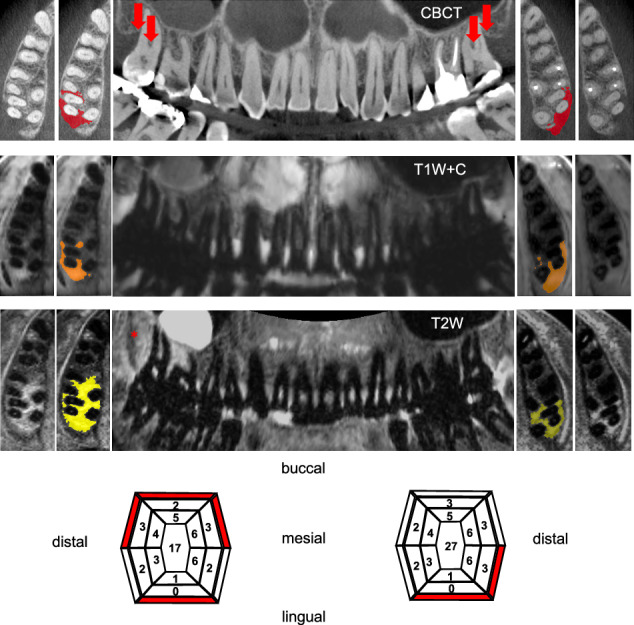

Methods: In this cross-sectional study nineteen patients with severe periodontitis underwent standardized clinical examination as well as pre-treatment CBCT and 3T-dMRI. Bone lesion volumetry was performed in CBCT, contrast-enhanced-T1-weighting (T1W + C) and T2-weighting (T2W) dMRI. Lesions whose T2W signal significantly exceeded T1W/CBCT margins (indicating excessive edema) were classified as T2W-mismatch. Volumetric data were compared to clinical findings.

Results: Ten female and nine male patients with 253 bony lesions were examined. Reliability for bone lesions was highest in CBCT (ICC [95% CI] T1W + C/T2W/CBCT: 0.78 [0.74-0.83]/0.82 [0.77-0.85]/0.87 [0.94-0.89]). Overall, T1W + C and T2W dMRI strongly correlated with CBCT (rs = 0.86 [95% CI: 0.82-0.89], p < 0.001 and rs = 0.91 [95% CI: 0.88-0.93], p < 0.001 respectively) but volume was significantly overestimated by dMRI (median percentage error of T1W + C-T2W: 19-55%). A T2W-mismatch was found in 44.1% and correlated with bleeding (85.8% vs. 70.9%, p = 0.005), giving 47.5% sensitivity and 71.2% specificity.

Conclusions: While dMRI offers good reliability, T2W- and to a lesser extent T1W + C imaging overestimate infrabony and interradicular periodontal bone lesion volumetry compared to CBCT. While this could increase the risk of overtreatment, dMRI detects periodontal inflammation beyond areas of bone loss, and T2W-mismatch is closely related but not identical to signs of active inflammation in clinical examination. This may provide additional diagnostic information and could serve as a supplemental tool for higher-risk patients.